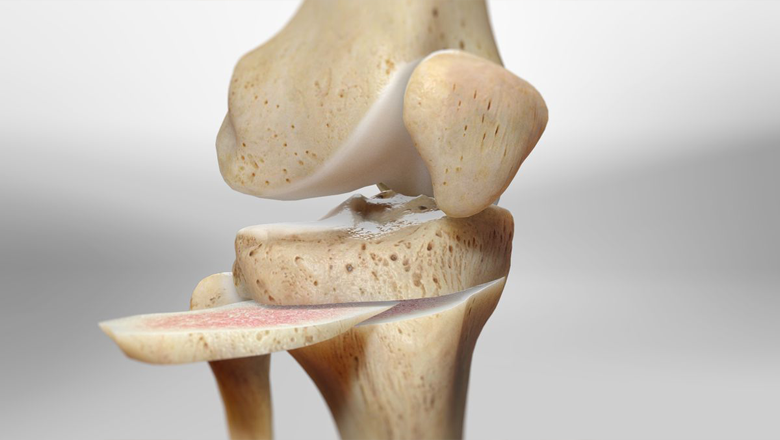

Partial Knee Replacement (PKR)

We carry out Partial Knee Replacement (PKR) for patients with early-stage knee damage, aiming to preserve as much healthy bone and tissue as possible while improving movement and reducing pain.

Best For:

- Early arthritis of knee

- Unicompartmental arthritis